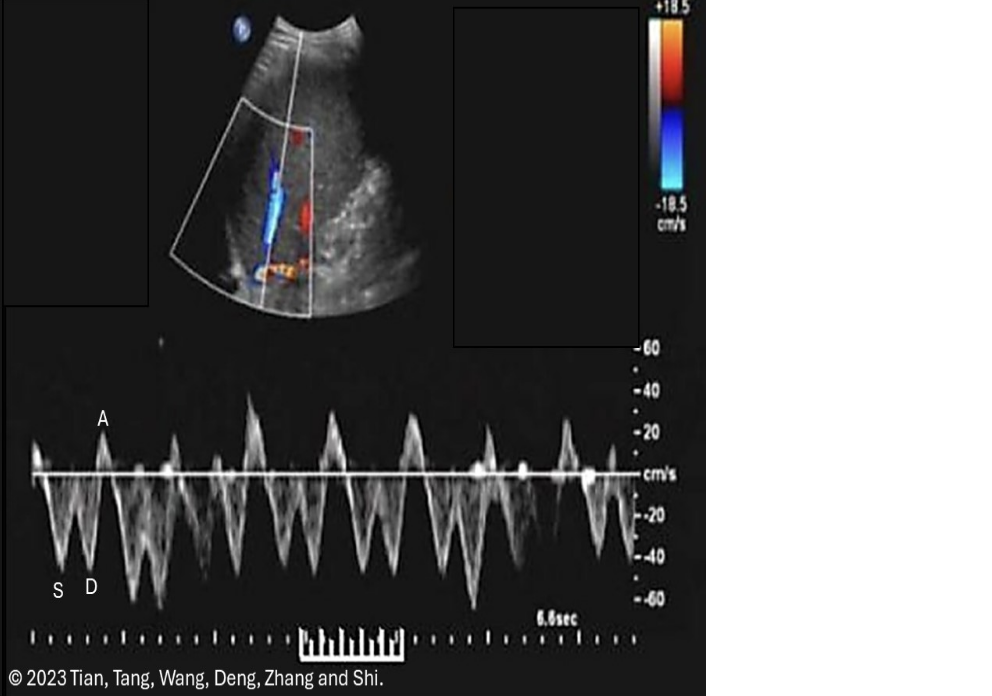

![<p>which describes a normal renal artery waveform</p><p>.</p><p>a) low resistance w/increased diastolic flow</p><p>b) increased diastolic flow reversal</p><p>c) biphasic w/mild diastolic flow reversal</p><p>d) pulsus alternans [methodical variation in peak vel on every other beat]</p>](https://knowt-user-attachments.s3.amazonaws.com/8c8e8b11-eaa0-4474-8147-a50abca9736d.png)

which describes a normal renal artery waveform

.

a) low resistance w/increased diastolic flow

b) increased diastolic flow reversal

c) biphasic w/mild diastolic flow reversal

d) pulsus alternans [methodical variation in peak vel on every other beat]

a. low resistance w/increased diastolic flow